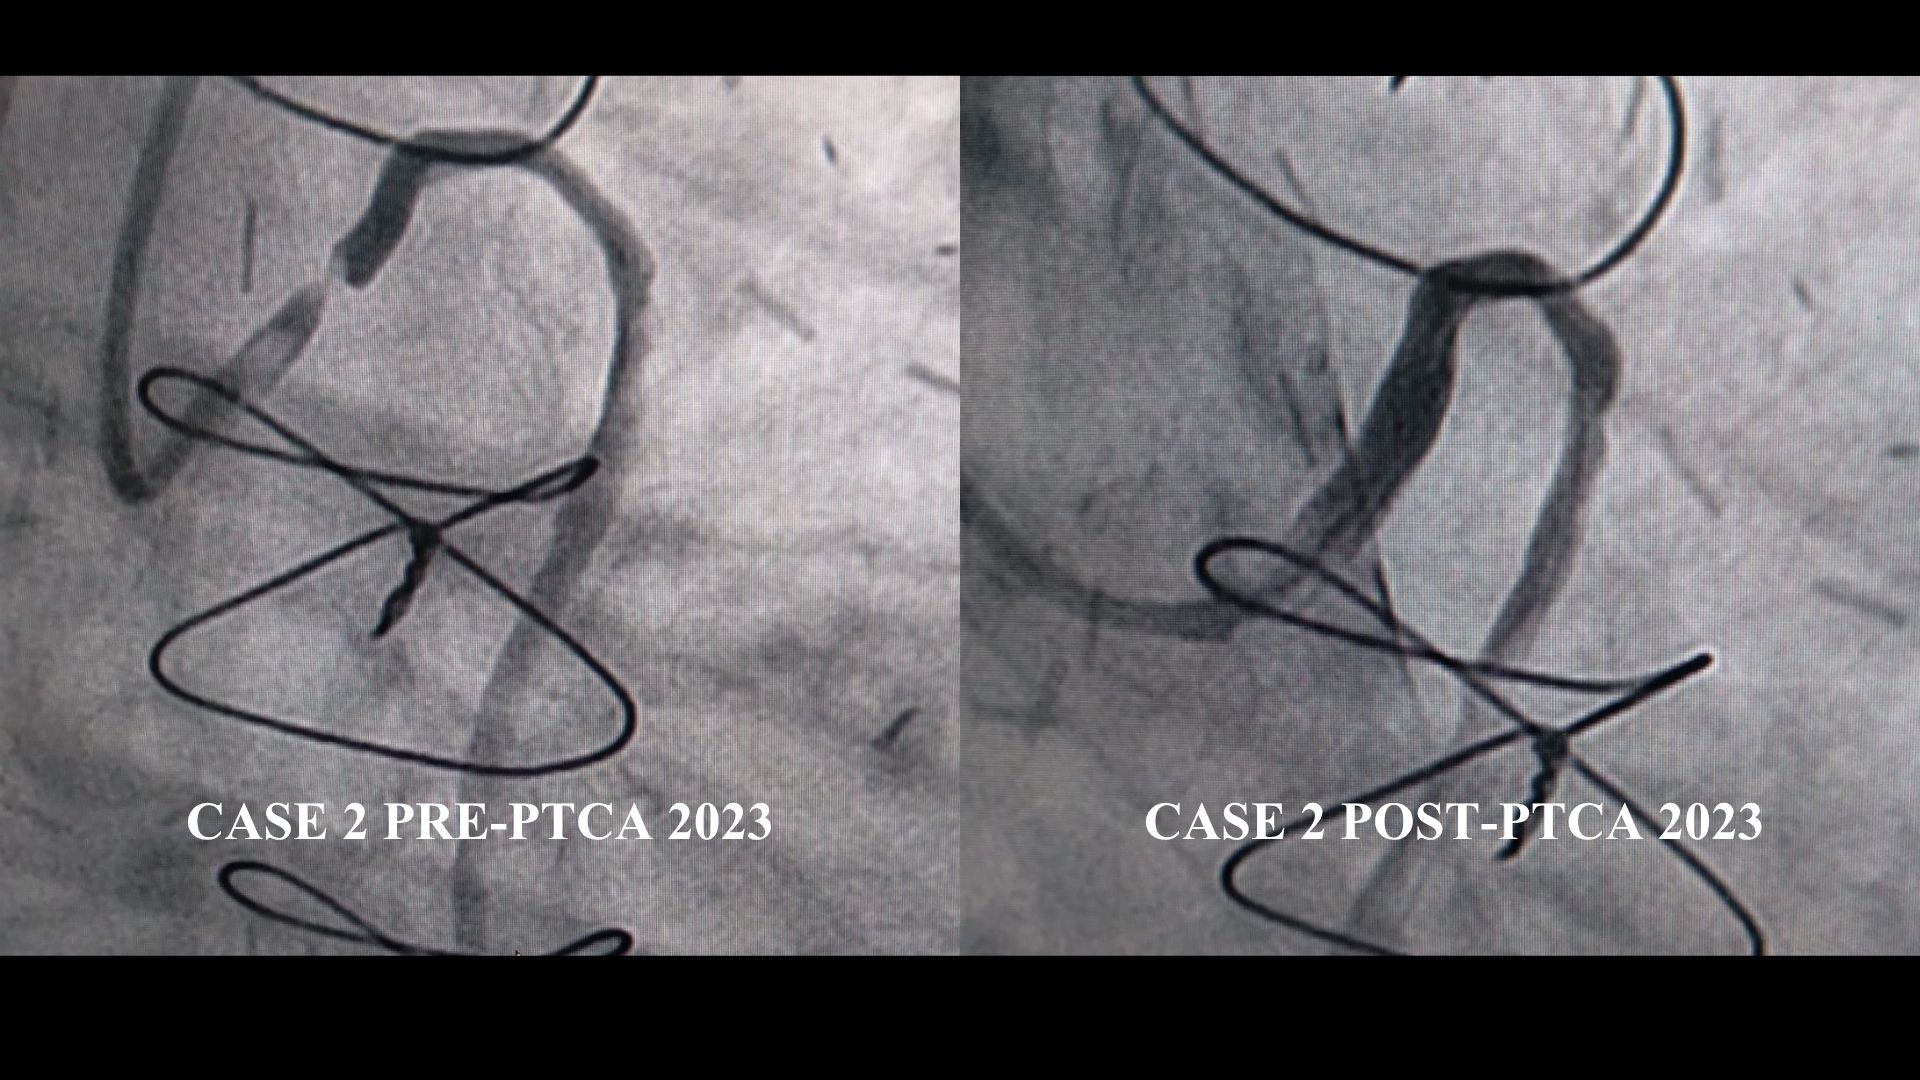

Case 1 – Angiography showed severe native left and right multivessel disease. Pedicle LIMA and RIMA grafts were patent with good distal flow. The free radial graft had a focal 90% stenosis at the distal edge of the prior stent. Case 2 – Severe native left and right multivessel disease was noted. LIMA–LAD graft patent with good flow. Free RIMA graft to RCA showed 40% proximal lesion with good distal flow. SVG–OM had a new 95% mid-graft stenosis beyond the previous stent without restenosis.

Case 2 – The SVG graft was cannulated using a 6F 3DRC guiding catheter. The lesion was crossed with a TurnTrac wire and predilated with a 2.5 ¡¿ 15 NC Trek balloon. Subsequently, a 2.75 ¡¿ 38 mm Xience Sierra stent was deployed beyond the distal edge of the previous stent, covering the entire lesion. TIMI III flow was achieved in the distal OM with good result. As this represented an acute ST-elevation myocardial infarction due to a recurrent SVG lesion, the patient received an intravenous bolus of Tirofiban followed by a 12-hour infusion. The recovery was uneventful.